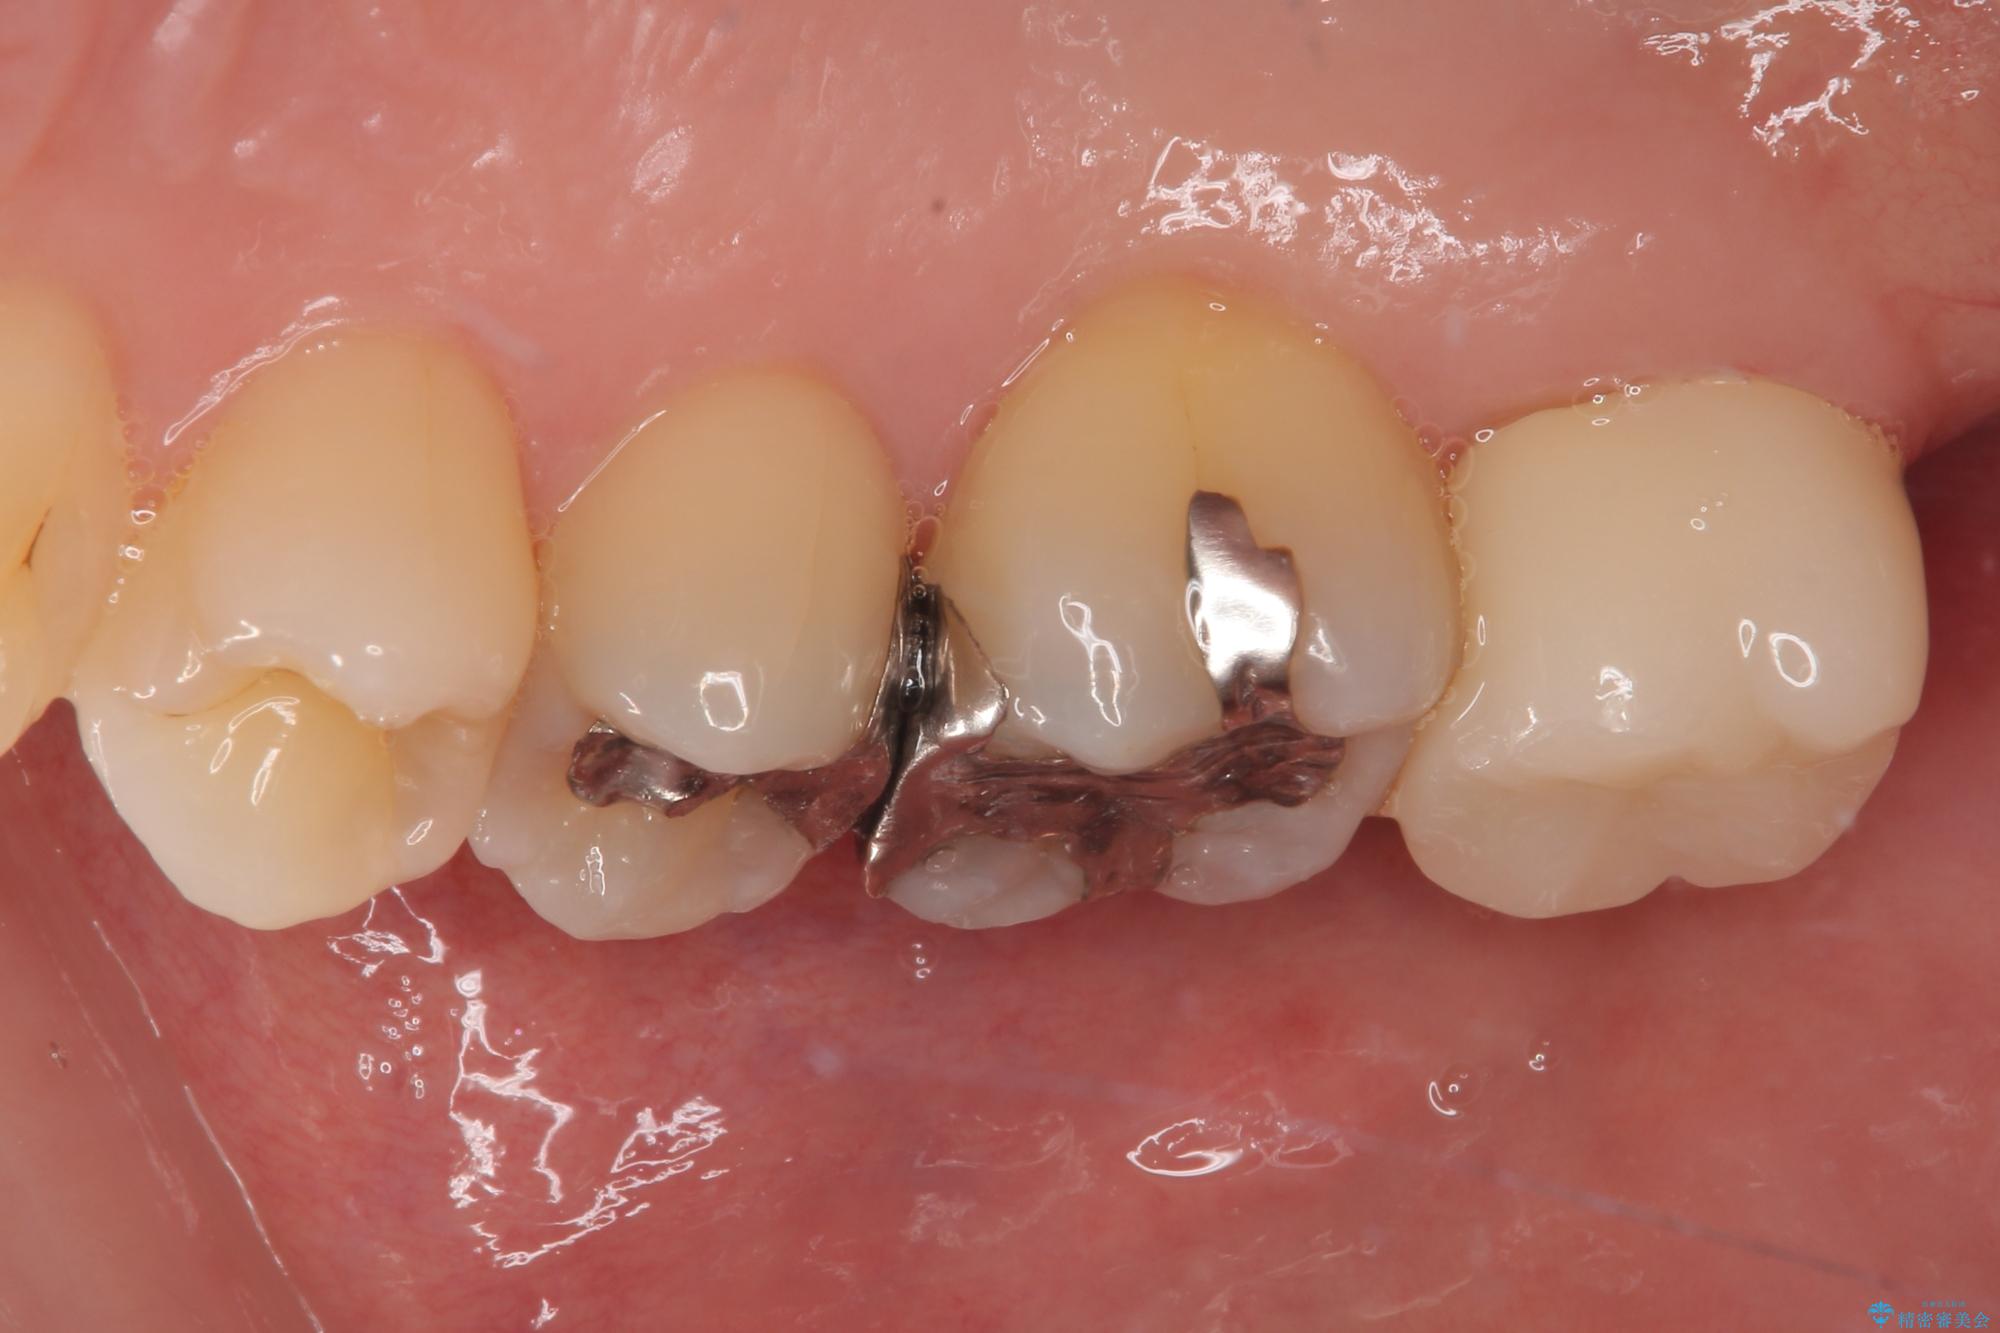

- 元々むし歯があったものの、処置が困難とのことでしたが、矯正治療を終えたので処置をしたいとのことで来院された患者様です。

左右ともに最後臼歯が頬側に顕著に突出しており、むし歯になってしまったことが想像されました。

矯正治療により処置が可能な位置に歯が移動したため、オールセラミッククラウンにて補綴治療を行うこととしました。

歯列が移動したとはいえ、左右ともに後方傾斜しており、むし歯の除去、形成(形を整える)、型取りの全てが非常に困難な処置となりました。

セラミッククラウンの適合はレントゲン写真からも分かる通り、境界がぴったりと合った、高適合のものとなりました。